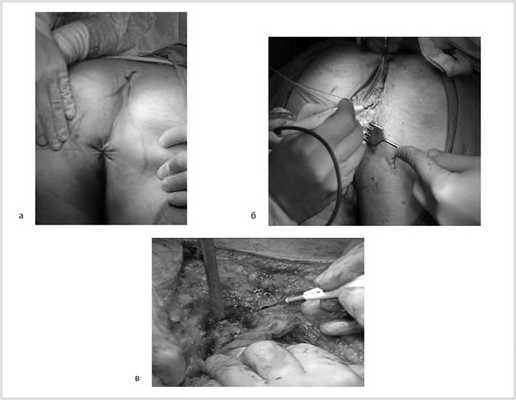

07.11.2012 выполнена цилиндрическая или экстралеваторная экстирпация прямой кишки. Через тазовую брюшину в мезоректальной клетчатке справа пальпируется верхний полюс опухоли, подрастающей к стенке прямой кишки, опухоль фиксирована к правой боковой стенке таза. Отдаленных метастазов нет (рис. 4).

Рис. 4. Этап операции. Ревизия опухоли.

Произведена мобилизация прямой кишки по левой и задней полуокружности, а также пресакрально до мышц тазового дна с соблюдением всех онкологических правил (рис. 5). По левой боковой стенке таза опухолевая капсула интимно прилежит к внутренней подвздошной вене и артерии, острым путем последняя мобилизована от магистральных сосудов.

Рис. 5. Этапы операции. а — мобилизация слева; б — мобилизация справа.

Далее сигмовидная кишка пересечена на уровне ее дистальной трети, а прямая кишка погружена в малый таз, при этом тазовая брюшина ушита над заглушенной культей прямой кишки. Затем сигмовидная кишка забрюшинно выведена в левом боковом отделе живота на переднюю брюшную стенку и сформирована плоская колостома, после чего брюшная полость ушита наглухо послойно (рис. 6).

Рис. 6. Этапы операции. а — ушивание тазовой брюшины; б — сигмостома.

Далее больной перевернут на живот в положении по типу «перочинного ножа» (рис. 7).

Рис. 7. Положение больного на столе (а). Вид операционного поля промежности (б).

После обработки операционного поля мобилизация прямой кишки продолжена из широкого промежностного доступа. Выполнено ушивание заднего прохода кисетным швом, намечены края резекции. В проекции крестцово-копчикового сочленения кожа и подкожная жировая клетчатка рассечены до задней крестцово-копчиковой связки. Последняя пересечена в поперечном направлении. Выполнена ампутация копчика с последовательным пересечением передней крестцово-копчиковой и крестцово-прямокишечной связок (рис. 8).

Рис. 8. Этапы операции. а — ушивание ануса; б — рассечение кожи и подкожной жировой клетчатки; в — пересечение крестцово-копчиковых связок.

Далее прямая кишка с опухолью в едином блоке мобилизована острым путем от предстательной железы и правой стенки таза, после чего выполнена цилиндрическая брюшно-промежностная экстирпация прямой кишки. Малый таз дренирован двумя силиконовыми дренажами и ушит наглухо (рис. 9).

Рис. 9. Этапы операции. а — мобилизация простаты; б — дренирование малого таза; в — конечный вид раны.